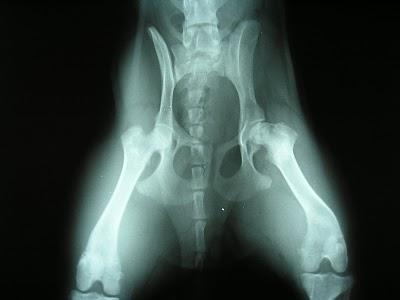

La malattia di Legg - Perthes Calve’ e'una patologia della testa del femore causata da una carenza dell'afflusso del sangue alla testa del femore durante l'età dello sviluppo, a causa di questa alterata irrorazione l'osso "muore" dando come risultato perdita di tessuto osseo con conseguente collasso della struttura ossea del collo e testa del femore che si deforma appiattendosi. La patologia riscontrata tra i cinque e gli otto mesi di età , le razze maggiormente colpite sono quelle toy , si manifesta all’inizio con una lieve zoppia con il progredire della malattia il cane sottrae l’arto al carico per il dolore intenso.

Una volta confermata la diagnosi di LPD il trattamento è di tipo chirurgico e consiste nel rimuovere la testa del femore danneggiata (osteoctomia della testa del femore).